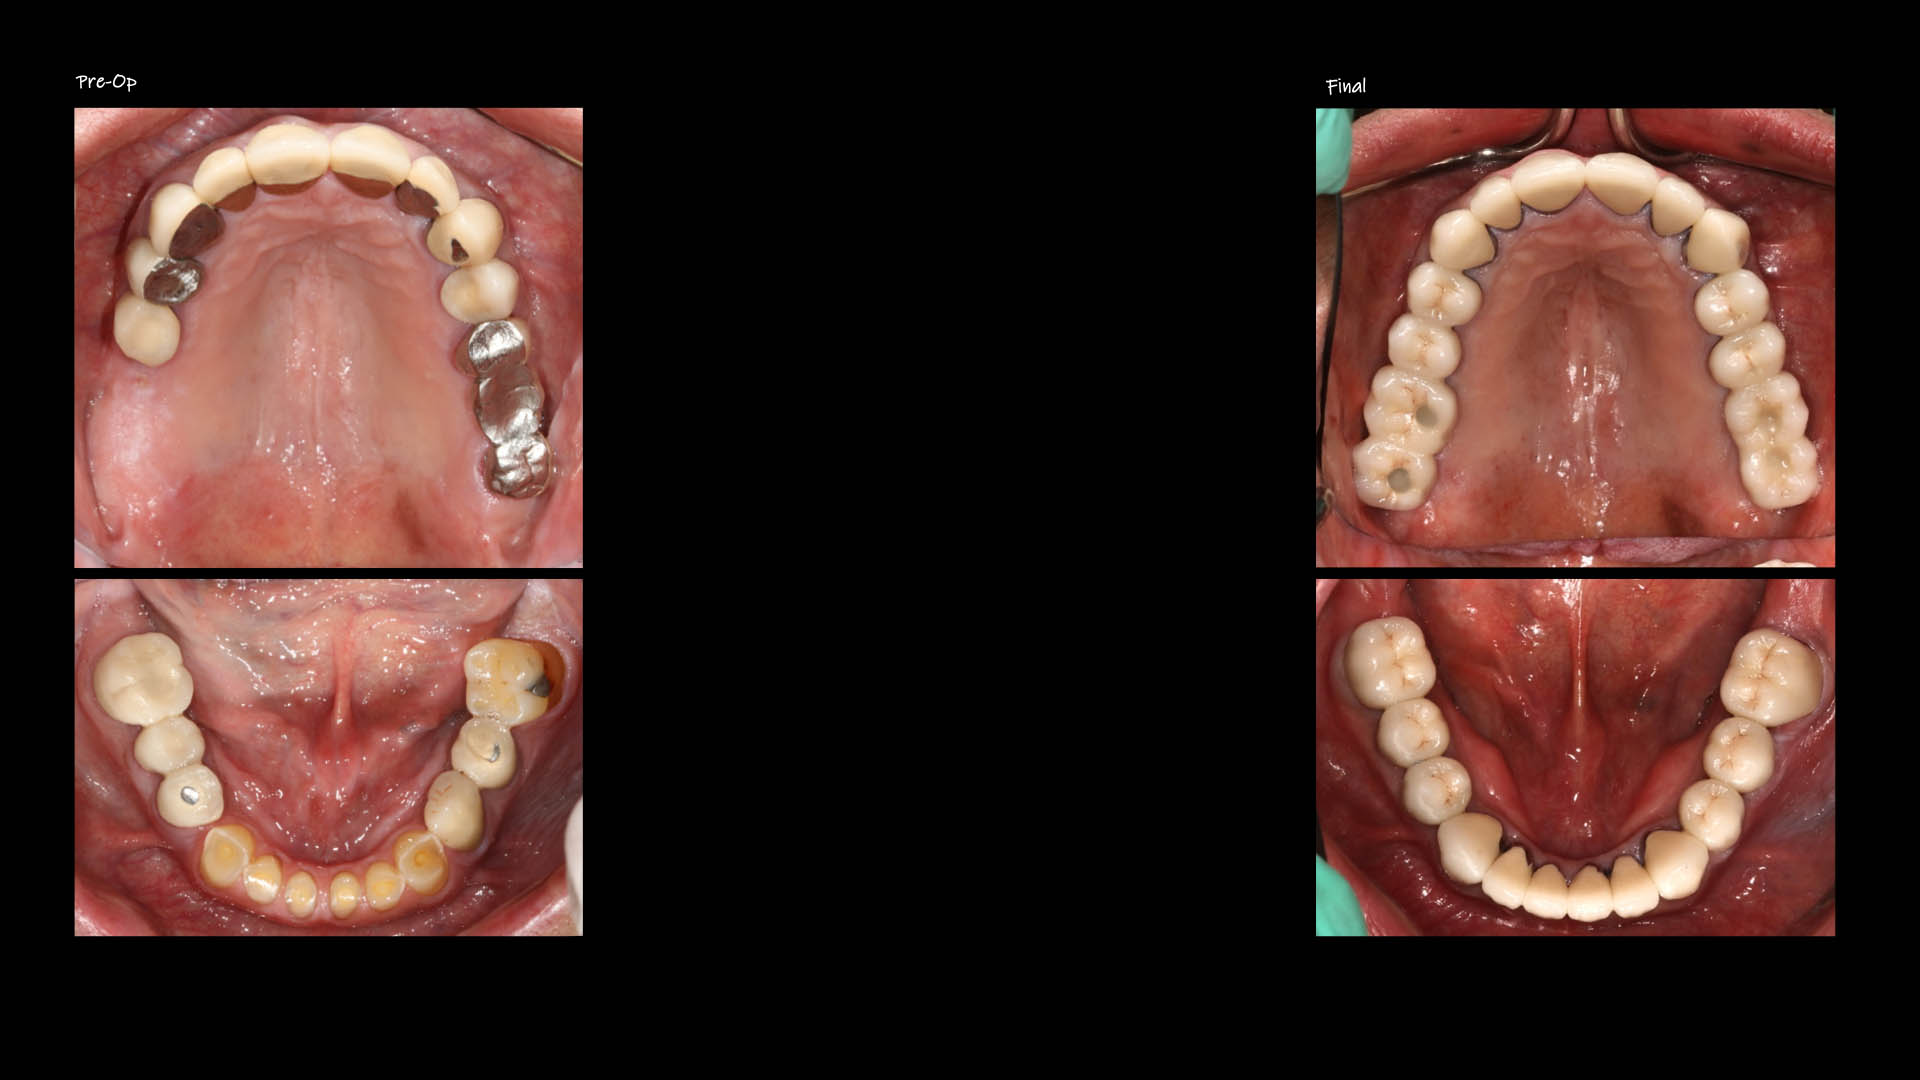

Take a glimpse into the magic of Coral Gables Dentistry through our before and after pictures. See firsthand the incredible smile makeover transformations that have brought confidence and joy to our patients.